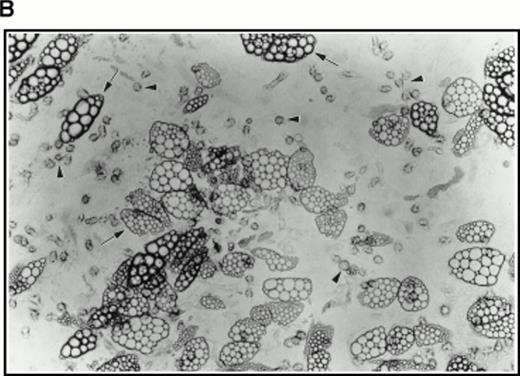

Aspirated bone marrow cells were separated on Ficoll and the mononuclear cell fraction isolated. These cells were then incubated for 7 days in medium supplemented with soluble human SCF, IL-3, and 5-FU. A sample of cells from a such a culture at 4 days of incubation is shown in Fig 4A (top right panel), together with a control culture in which the 5-FU was omitted (Fig 4A, top left panel), by way of comparison. A strikingly different picture was observed in the presence of 5-FU with the majority of the surviving cells being terminally differentiated cells such as erythrocytes and polymorphs. Large cells with expanded nuclei and prominent cytoplasm frequent in the untreated cultures were conspicuous by their absence. To show that the cells surviving the 5-FU treatment were quiescent, 24 hours before harvesting, tritiated thymidine was added to the cultures to label any dividing cells. After 7 days of culture in the selective medium, the cells were collected onto microscope slides by Cytospin and dipped in autoradigraphic emulsion. Prominent clusters of silver grains could be seen in untreated control cultures (Fig 4A, middle left panel), whereas cells from the 5-FU–treated culture were unlabeled (Fig 4A, middle right panel). The cells were also analyzed for high-level expression of the SCF receptor, a marker for the 5-FU–resistant cells.3 As shown in Fig 4A, the 5-FU–resistant cells (bottom right panel) all showed bright fluorescence with a FITC-conjugated anti-SCF receptor antibody, whereas the untreated controls (bottom left panel) showed a wide spectrum of intensities, confirming that 5-FU selects a subset of cells with a higher level of expression of SCF receptor.

(A) Selection of quiescent bone marrow cells using 5-FU. Bone marrow mononuclear cells were incubated for 7 days in IMDM either supplemented with IL-3, SCF, and 5-FU to kill dividing cells (right-hand panels) or not (left-hand panels). At 4 days of incubation an aliquot was spun onto microscope slides and stained with Wright’s stain (top panels). Twenty-four hours before harvesting, 3H thymidine was added to the cultures. Following 7 days incubation cells were obtained and spun onto microscope slides. The slides were dipped in photographic emulsion and exposed for 7days before being developed, counterstained with Wright’s stain, and visualized under the light microscope (middle panels). (Bottom panels) Cells as above, but stained with antibody to c-kit and viewed under fluorescence. (B) Long-term culture. 5-FU–selected cells were plated on monolayers of bone marrow derived fibroblast as described in Materials and Methods and used to initiate long-term bone marrow cultures. The arrows show areas of extensive lipid deposition characteristic of these types of culture. Arrowheads identify “cobblestone areas,” clusters of developing hematopoietic cells.

Very few cells survived this procedure. Indeed, as assayed by Trypan blue staining of a small sample, all visible cells were found to be nonviable. However, when used to initiate long-term cultures on preformed, irradiated stroma, this population of cells proved very active in establishing hematopoiesis as evidenced by extensive lipid deposition and characteristic “cobblestone” areas (Fig 4B).